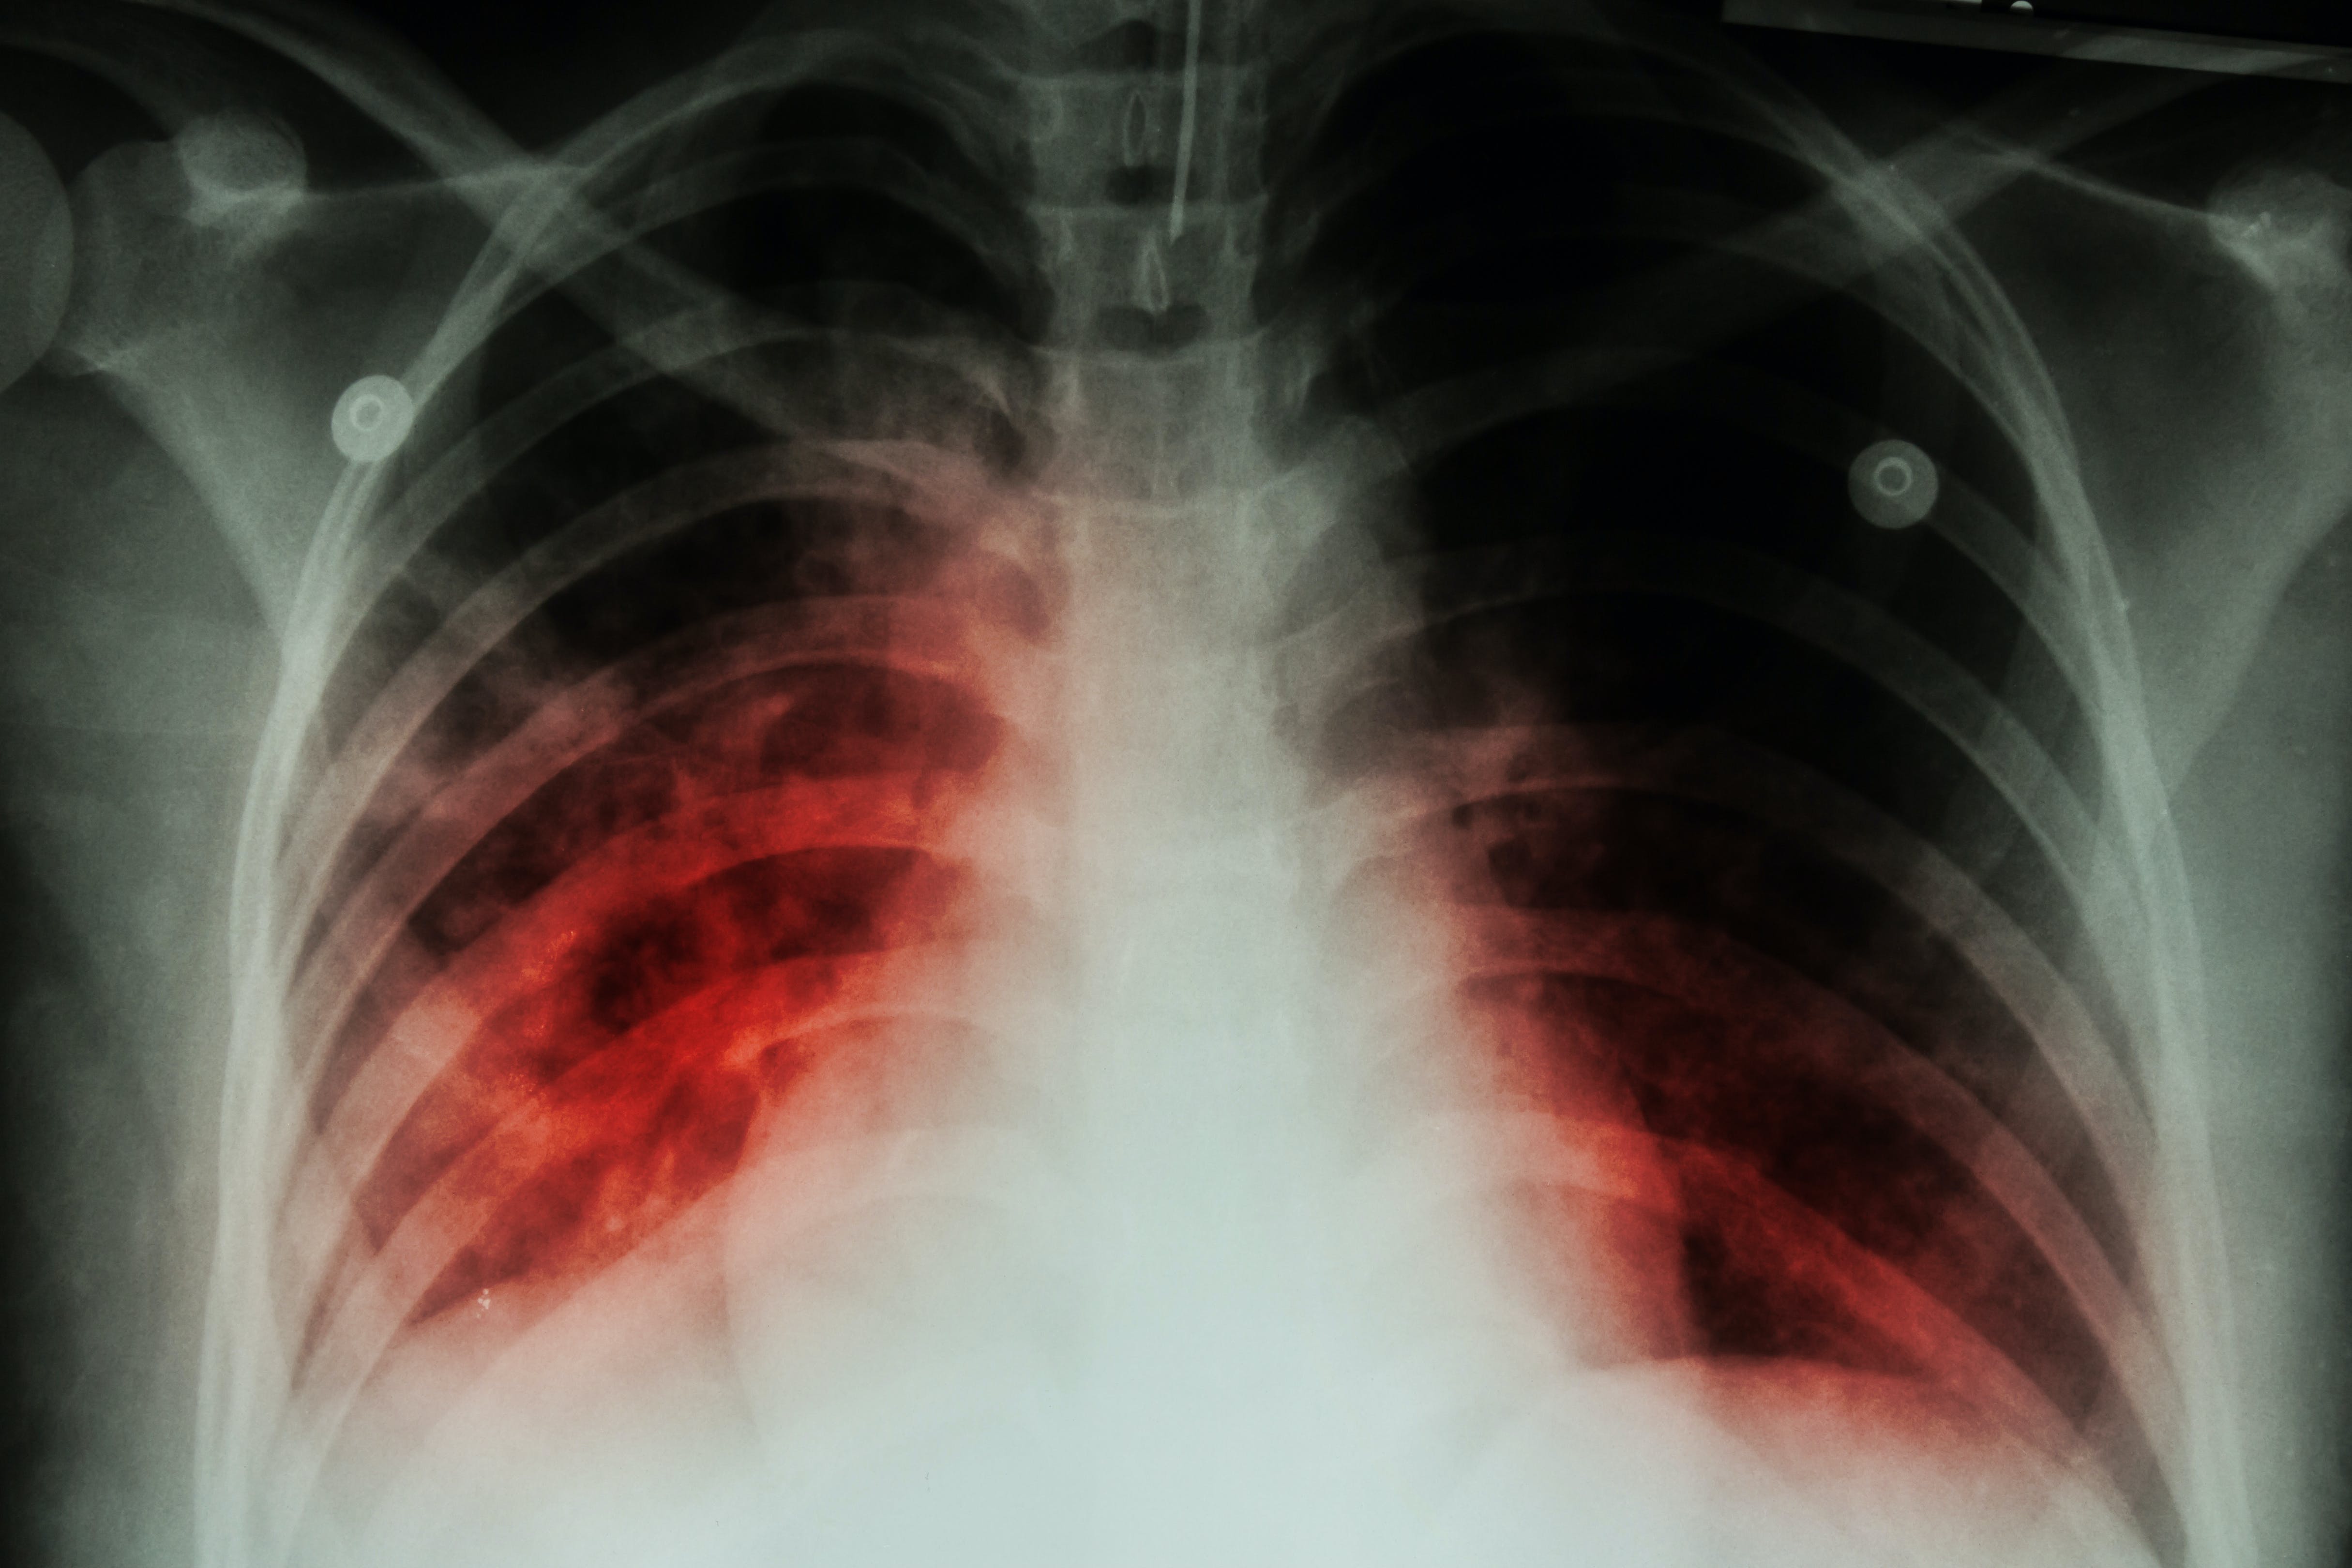

Effective TPT in people at highest risk of progression safely reduces the likelihood of developing TB disease. This includes individuals exposed to multidrug- or rifampicin-resistant TB (MDR/RR-TB).